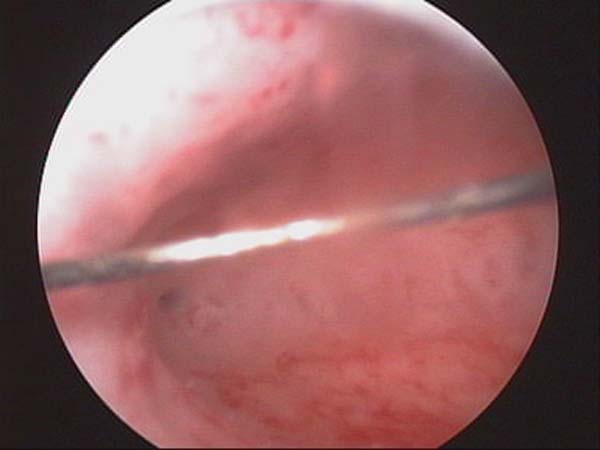

- Hysteroscopy Video clips

- Hysteroscopy Photos

Hysteroscopy Pictures | Dr N Layyous